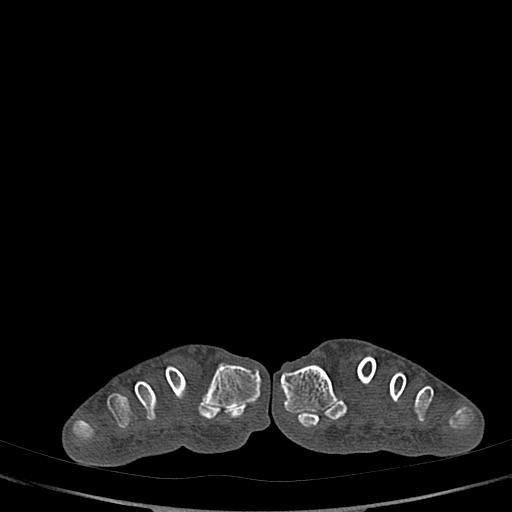

标题: CT13415:M72Y,跖趾关节病变,请会诊 [打印本页]

标题: CT13415:M72Y,跖趾关节病变,请会诊

男72岁左侧跖趾关节肿痛15年,查压痛。

考虑退行性骨关节病。